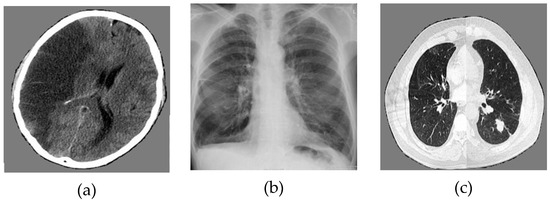

The numerical results are carried out in MATLAB16b environment. We use biomedical images of size 256 × 256 for cerebrovascular accident, pulmonary fibrosis, and lung cancer. Applying the encryption and decryption algorithm described below, the results for encrypted and decrypted biomedical images are shown in Figure 13.

Figure 13.

Numerical results: (a) initial image of cerebrovascular accident, (b) initial image of pulmonary fibrosis, (c) initial image of lung cancer, (d) encrypted image of cerebrovascular accident, (e) encrypted image of pulmonary fibrosis, (f) encrypted image of lung cancer, (g) decrypted image of cerebrovascular accident, (h) decrypted image of pulmonary fibrosis, (i) decrypted image of lung cancer.